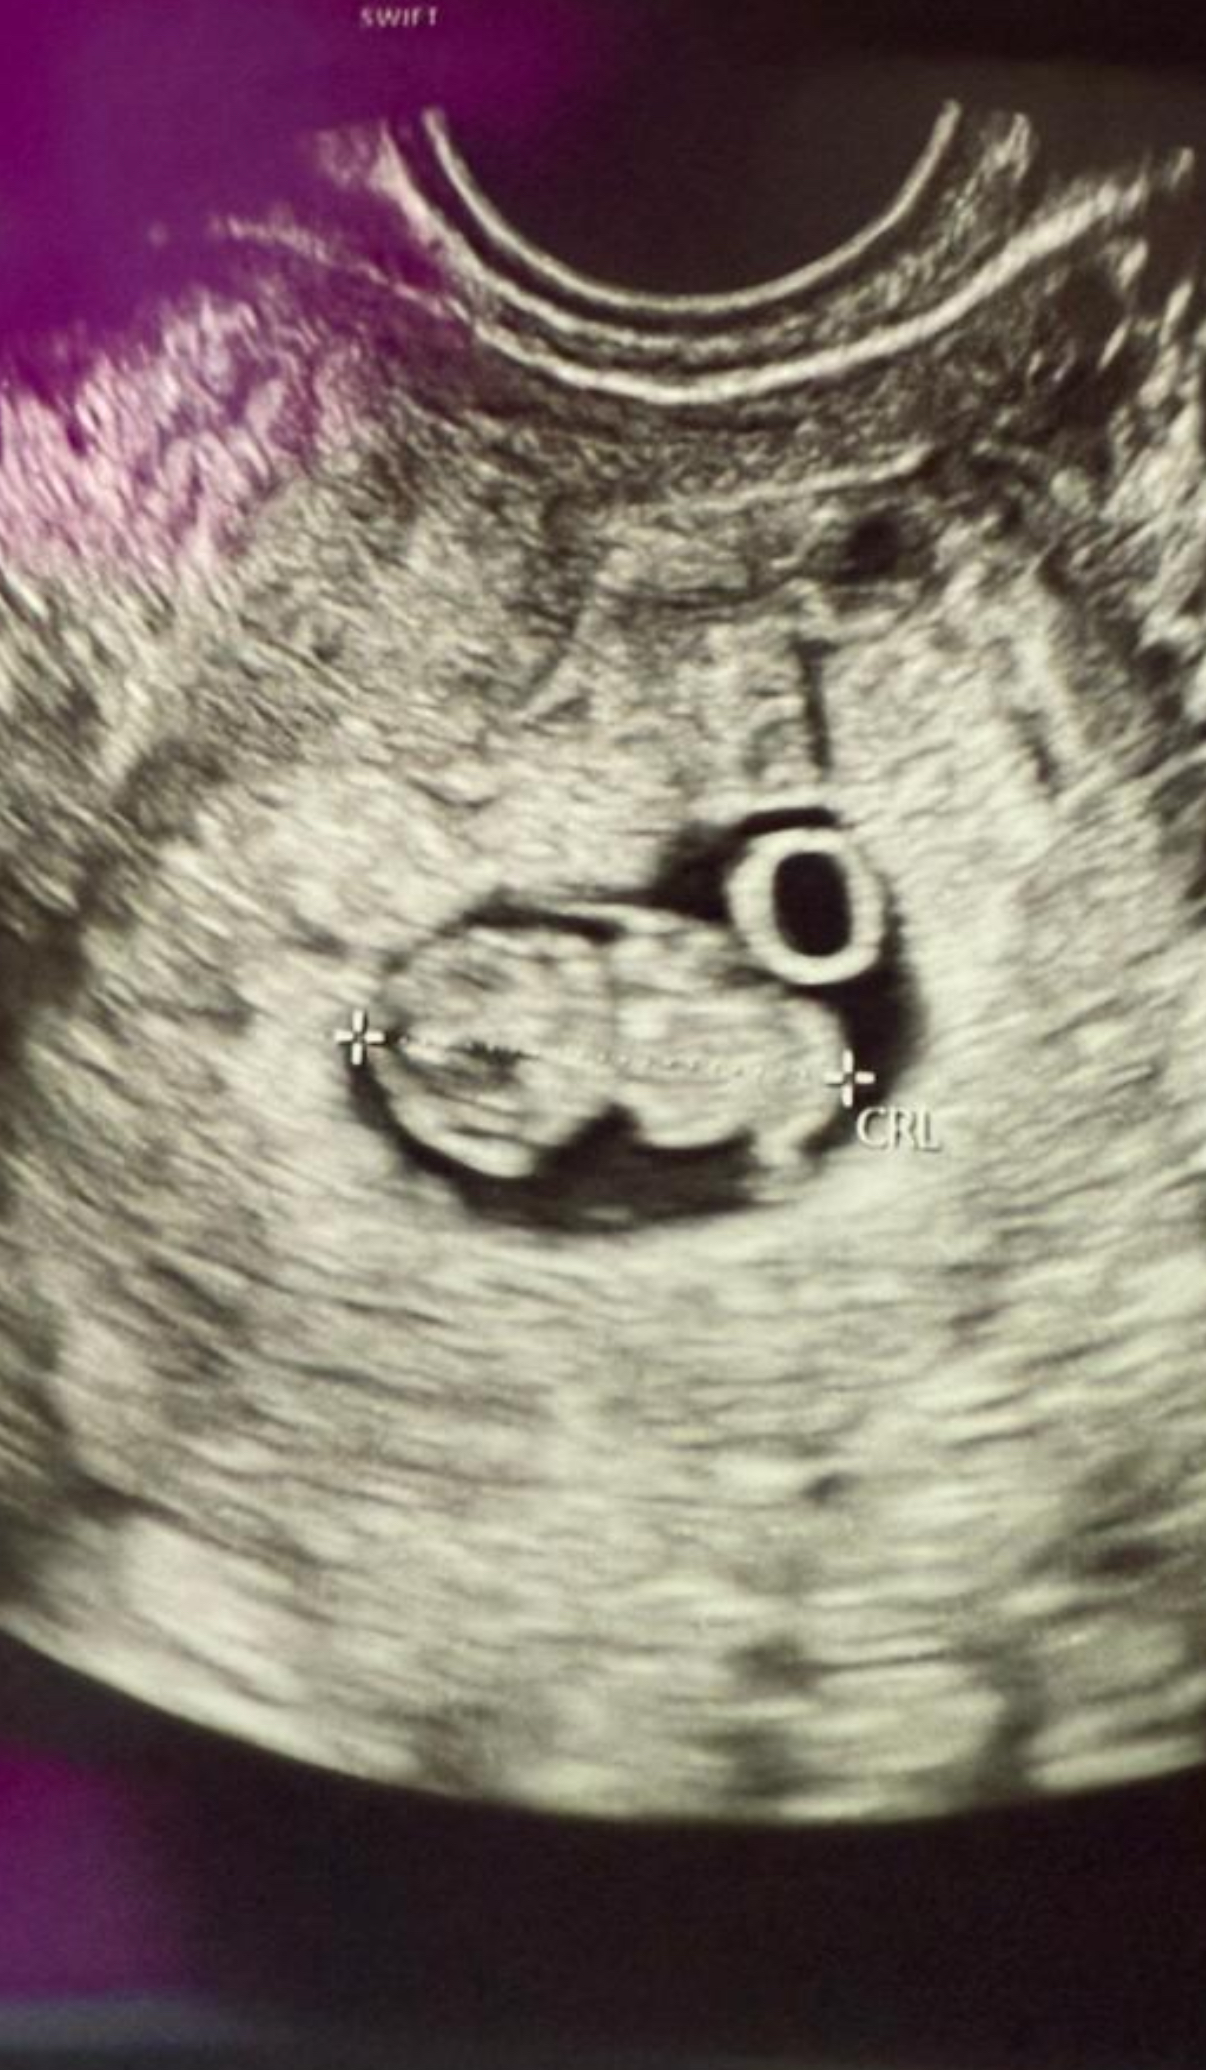

Awokado30 wrote:2 cm czystego cudu 💝

Serduszko biło jak szalone - aż 178 bpm 🥹

Termin porodu lekko się przesunął - teraz to 18 listopada 2026 💞

Badania prenatalne wypadają idealnie w moje urodziny - 6.05 🎂💝

Kolejna wizyta już za 4 tygodnie - 12.05 ✨